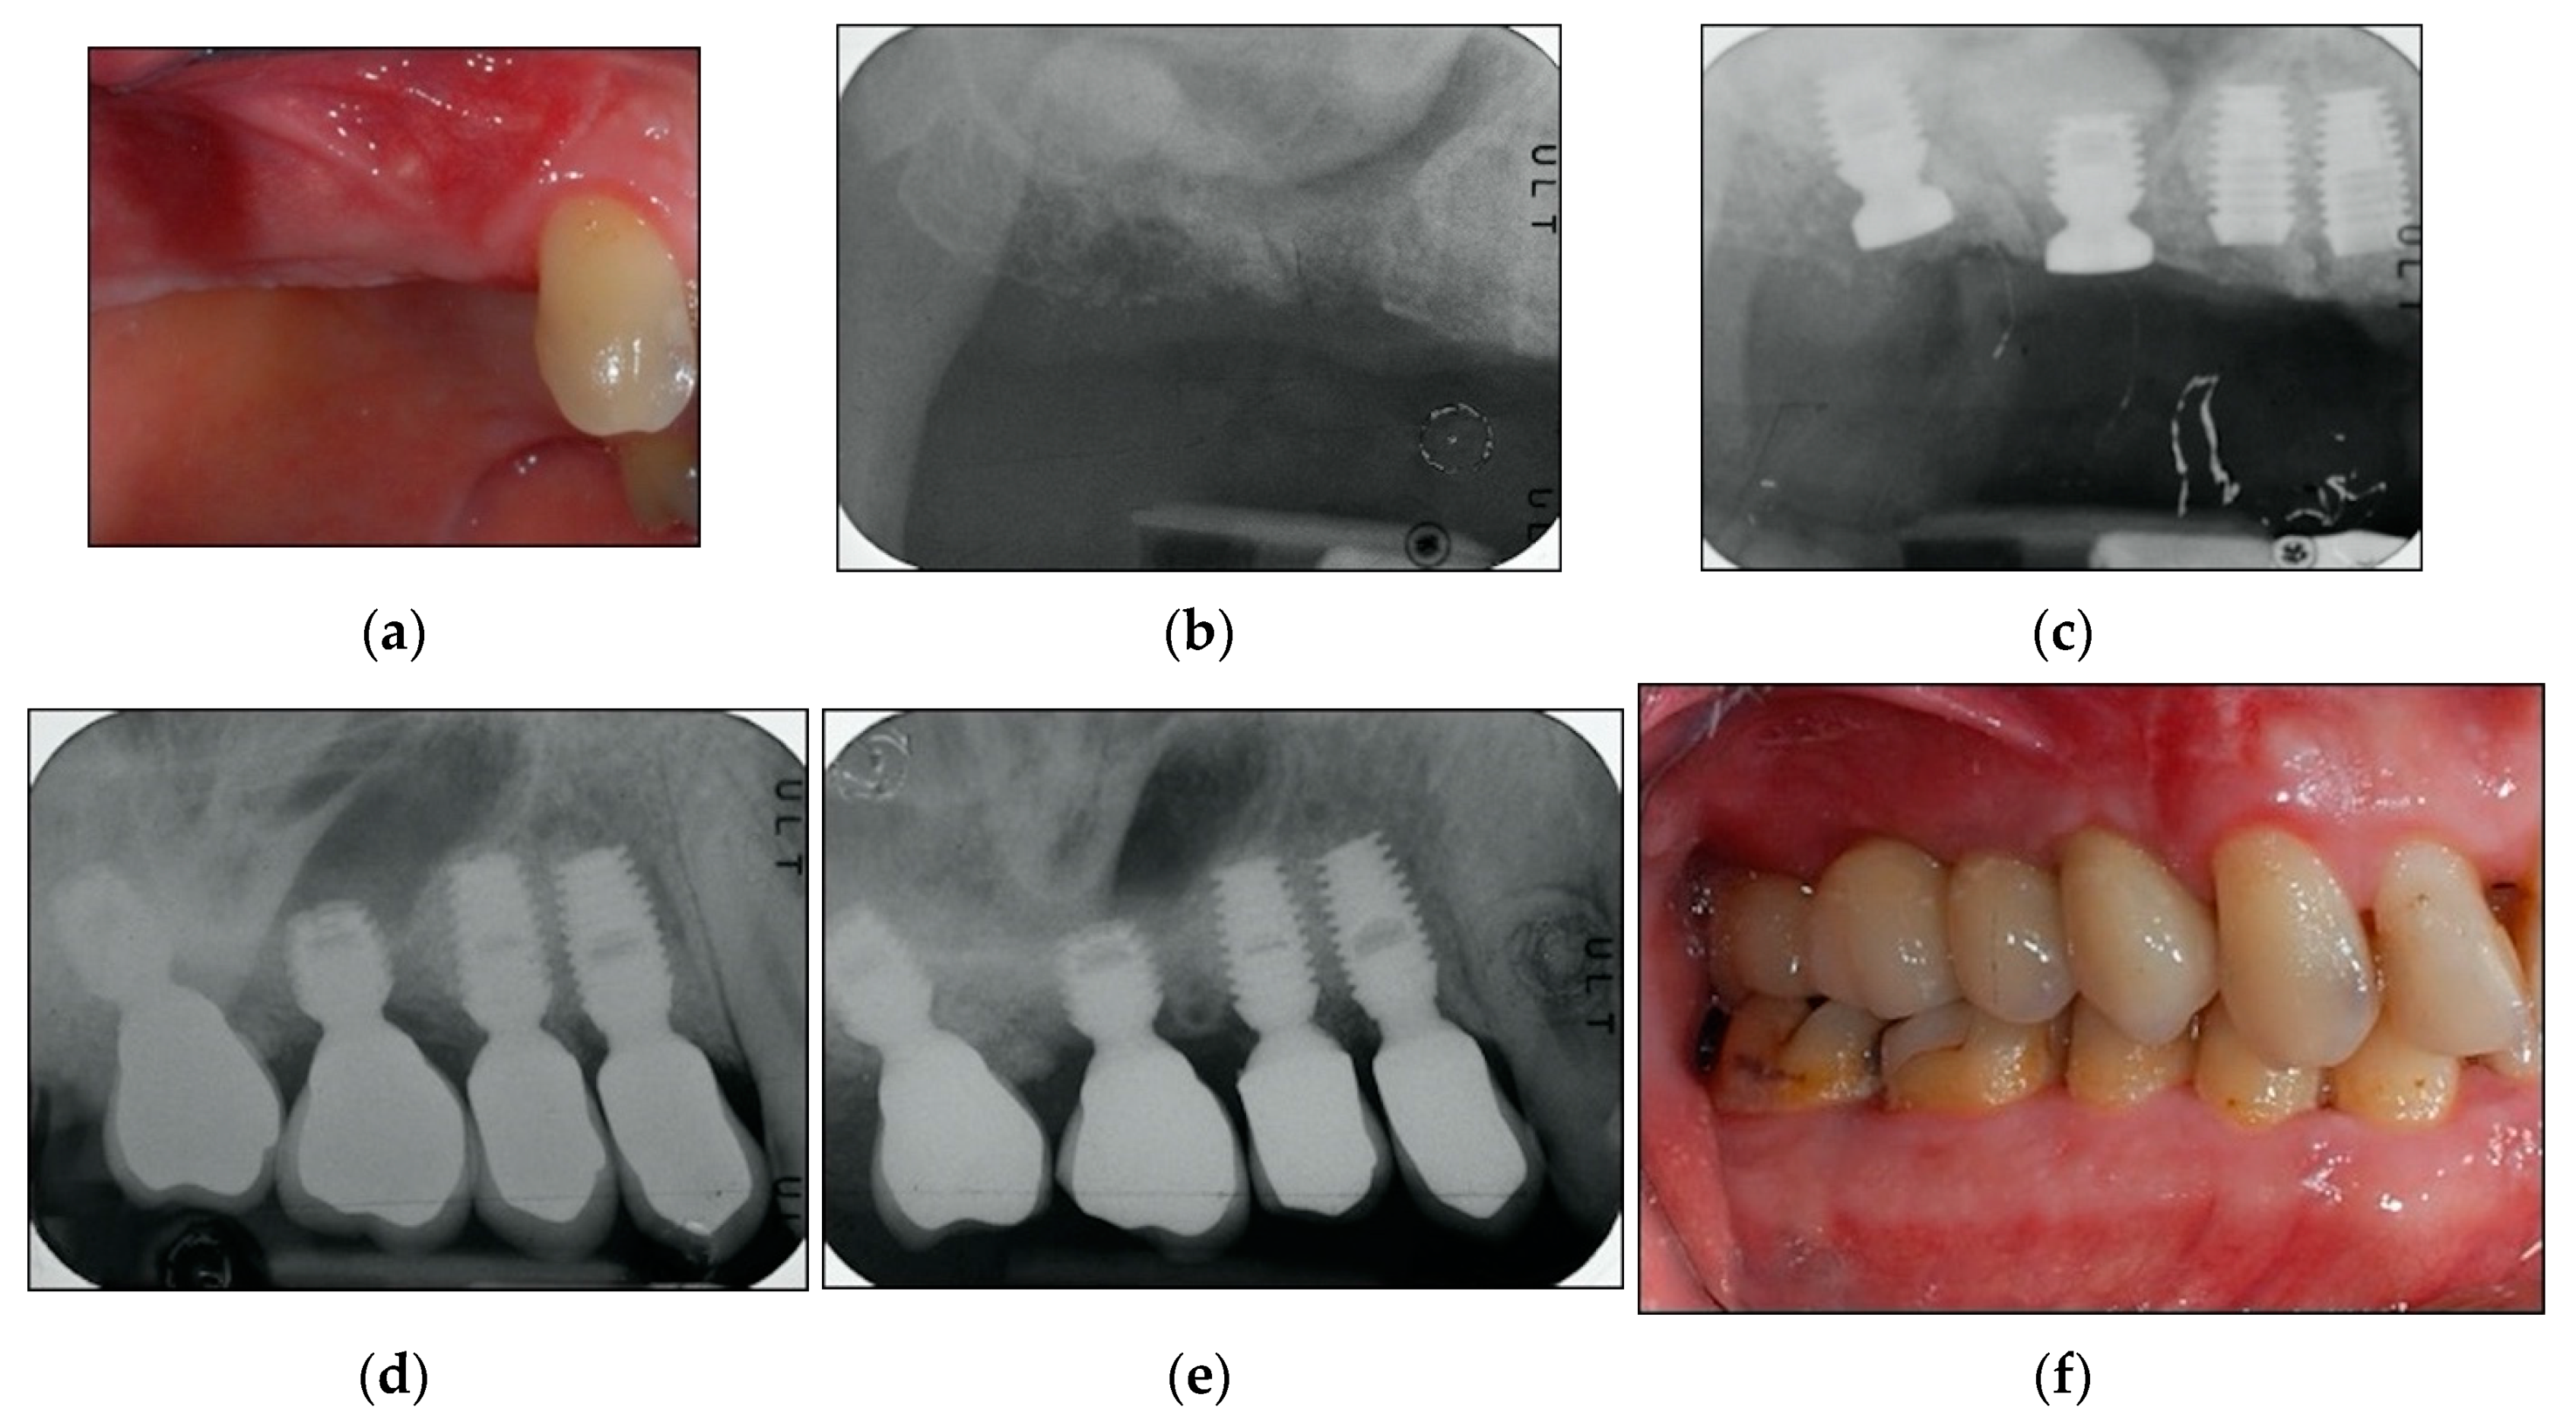

A maintenance program was designed to provide patients a professional oral hygiene session every four months [33] and home care procedures were reinforced. At each recall appointment, occlusion was assessed and adjusted as necessary; prosthetic restorations were checked for loosening, chipping, or other types of complications. Clinical assessment of peri-implant soft tissues and radiographic examinations were performed after three years of follow-up from loading time [29,30]. By way of illustration, Figure 2, Figure 3 and Figure 4 report some radiographic cases.

Figure 4. (ag). Clinical case: Four implants placed in 2.4, 2.5, 2.6, and 2.7 sites. (a) Clinical photograph before implants placement. (b) Pre-operative radiograph before implants placement in sites 2.5, 2.6, and 2.7. (c) Radiograph obtained at implants placement. See augmented sinus floor. (d) Radiograph obtained at loading time. Another implant was placed in site 2.4 (the extracted tooth had grade 3 mobility and was extremely compromised). Site 2.4 was temporarily restored using the implant in 2.5 site to support a cantilever prosthesis. (e) Radiograph obtained at loading time. See definitive restorations for all implants. (f) Radiograph obtained at three-year follow-up. See stable bone levels. (g) Clinical photograph at three-year follow-up. See stable clinical conditions.